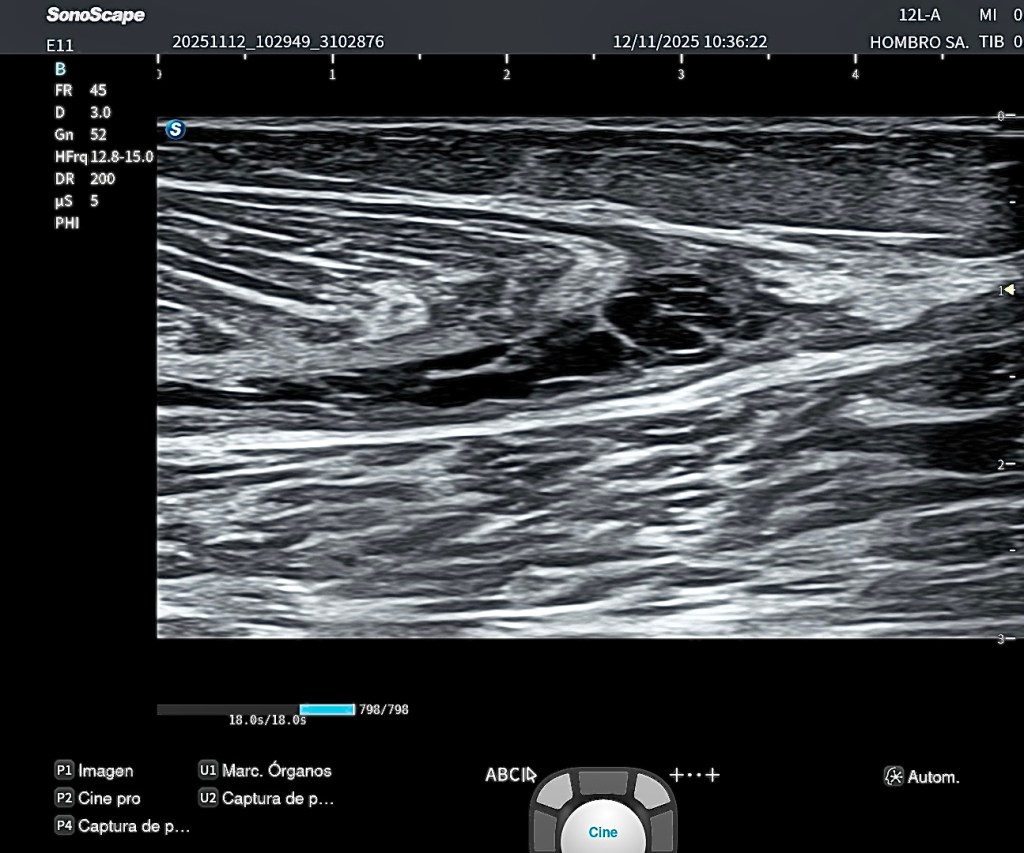

En esta imagen 1 se aprecia de forma muy clara la anatomía en un corte axial oblicuo del tercio medio del cuello anterolateral, una de las ventanas más útiles para el estudio ecográfico del plexo braquial.

En la porción medial identificamos el paquete vascular principal, formado por la arteria carótida y la vena yugular interna, que actúan como referencias anatómicas fundamentales. En un plano más superficial se observa el músculo esternocleidomastoideo, y aún más superficial, el músculo platisma.

Por debajo del esternocleidomastoideo y desplazándonos hacia lateral, aparece el músculo escaleno anterior, que constituye uno de los límites del espacio interescalénico.

Entre el escaleno anterior (medial) y el escaleno medio (lateral) se localiza el plexo braquial, en este nivel formado fundamentalmente por raíces y troncos, no por ramas terminales. Estas estructuras nerviosas presentan en ecografía un aspecto característico, ligeramente hipoecoico, con patrón fascicular, a menudo descrito como “racimo de uvas”.

Más lateral se identifica el músculo escaleno medio, y posteriormente el escaleno posterior, completando el grupo muscular profundo del cuello en esta región.

En el plano más profundo y lateral, se puede reconocer la primera costilla, que actúa como referencia anatómica clave y como límite posterior del espacio donde discurre el plexo.